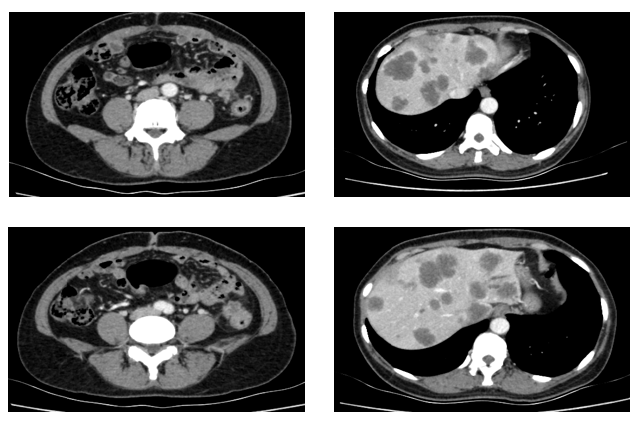

患者为51岁女性,因“间断腹痛半年余,进行性加重1月”于2021年3月就诊于我院结直肠外科。入院时胸全腹部CT(2021-3-29)提示:降结肠远端增厚,肝内多发占位,肺内多发小结节,考虑转移。肠镜检查:在距肛门28公分处,管腔狭窄,内镜不能通过。病理提示:腺癌。